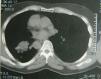

Un hombre de 46años de edad, no fumador y que no refería molestia alguna, fue derivado a nuestro servicio con una radiografía de tórax anómala que mostraba dextrocardia y una opacidad homogénea en la zona media del pulmón derecho. La tomografía computarizada (TC) de tórax reveló una atelectasia segmentaria, que se extendía desde el lóbulo inferior derecho hasta el lóbulo medio derecho (fig. 1). El corazón y el bazo también se observaban a la derecha de la línea media y el hígado se localizaba a la izquierda. Con estos hallazgos, se definió un SIT. La broncoscopia de fibra óptica reveló la ausencia de lóbulo superior en el pulmón derecho, pero es interesante destacar que la estructura del lóbulo superior del pulmón izquierdo era similar a lo habitual, es decir, incluía los 3 segmentos: apical, anterior y posterior. Los resultados del lavado broncoalveolar y de la citología fueron normales. El lavado broncoalveolar y el broncoaspirado fueron negativos para bacilos ácido-alcohol resistentes y el cultivo de Lowenstein para tuberculosis fue negativo. Con 6meses de seguimiento no se observaron cambios clínicos ni radiológicos.